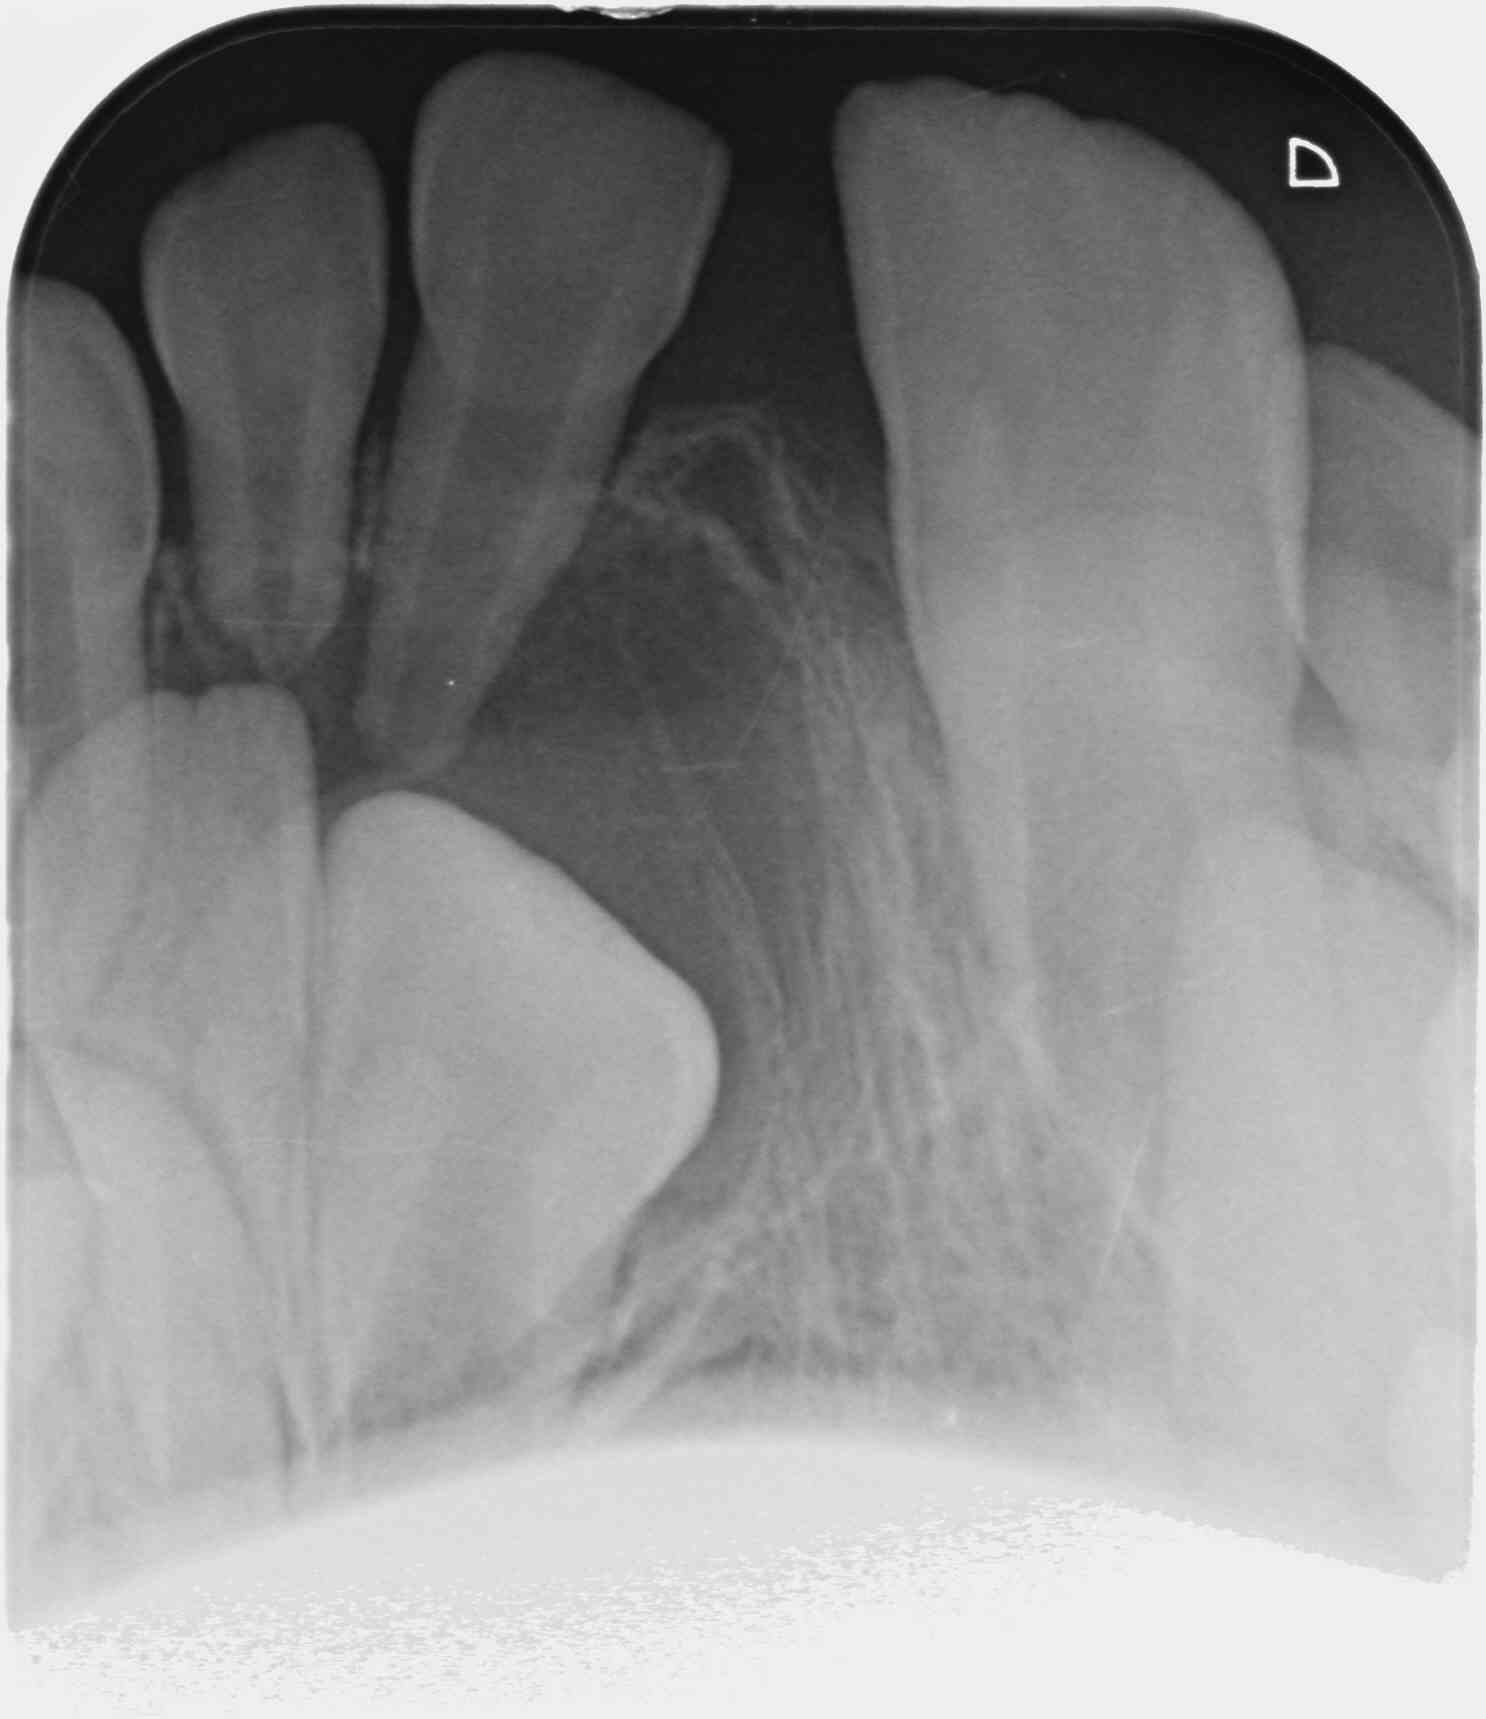

que feriez-vous pour la 21 bloquée, asymptomatique, chez un enfant de 8 ans ?

j'ai l'impression qu'il y a un kyste péricoronaire.....

de toutes façons tu risques pas grand chose à extraire les deux dents déciduales, bien nettoyer/faire le chemin et ré-évaluer dans quelques semaines....au pire çà se terminera en traction ortho....

Sans doute consécutif à un choc il y a quelques années ---> nécrose, infection et non rhizalyse de la racine de la 61.

Il faut extraire cette 61 et faire un contrôle dans trois mois et suivre l'éruption tous les 3 mois. Il y a un risque de malposition.